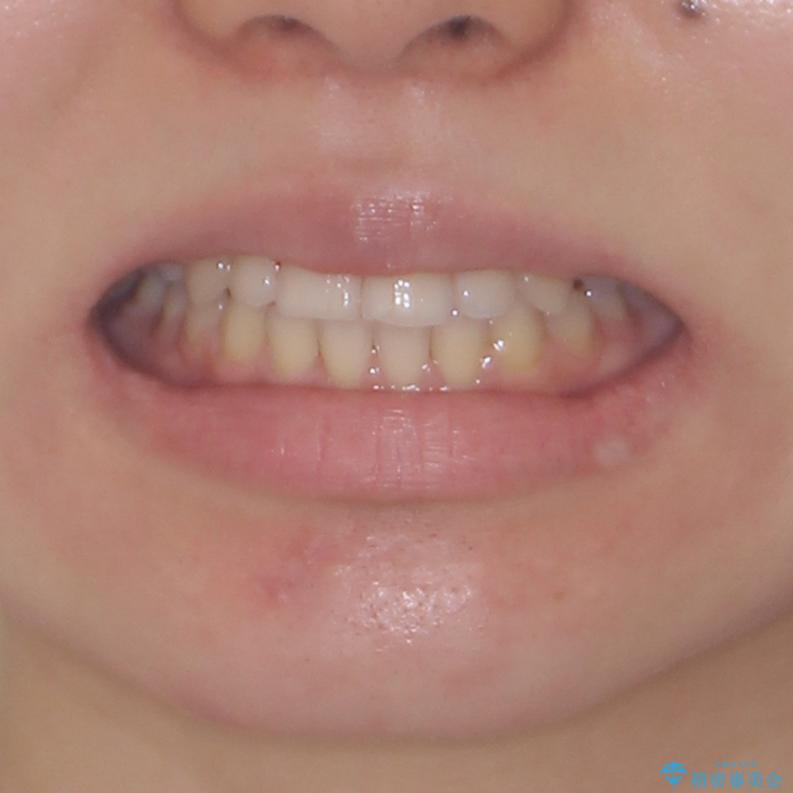

- 前歯のデコボコや八重歯、舌癖による開咬を気にして来院された患者様です。

補助装置を事前に使用したことで、あっという間に八重歯が改善し、ハーフリンガルにしては1年半もかからずに治療を終えることができました。